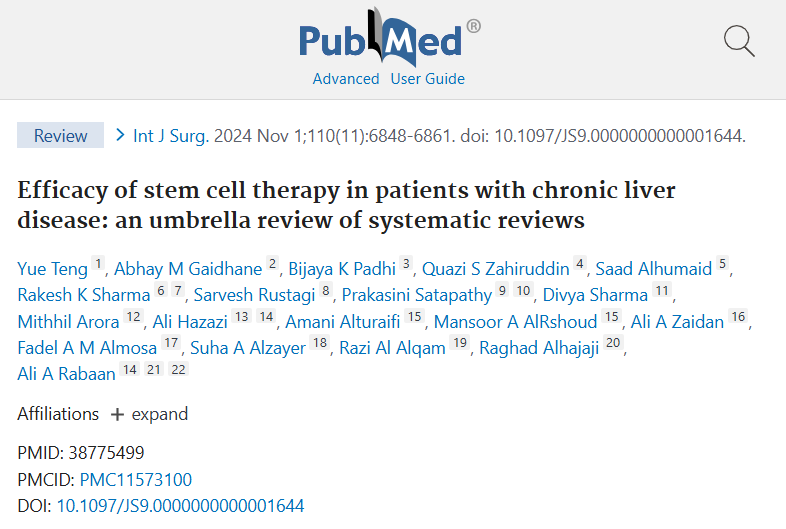

近年来,干细胞疗法为肝病治疗提供了新思路。干细胞具有自我更新和多向分化的潜能,可分为全能干细胞、多能干细胞和专能干细胞等类型。在肝病干预中,间充质干细胞是研究较多的一类。

多项临床研究表明,干细胞疗法在改善肝病患者生存率和肝功能方面显示出潜力。

提高生存率:对肝衰竭患者的随访研究发现,接受干细胞应用的患者在一定时间内的生存率优于对照组。

改善肝功能:部分终末期肝病患者在接受干细胞应用后,肝功能指标如ALT、AST、总胆红素等有所下降,白蛋白水平提升,临床症状如乏力、食欲不振等得到缓解。

安全性良好:干细胞免疫原性较低,不易引起剧烈免疫反应。目前常见不良反应主要为短暂发热,多可自行或经简单用药后缓解,严重并发症报道较少。

现有研究表明,干细胞在特定条件下能分化为具有功能的肝细胞,参与肝功能修复,为肝病干预提供了新的方向。随着科研与临床的不断深入,干细胞疗法有望成为肝病干预的重要手段之一,为更多患者带来希望。

https://pubmed.ncbi.nlm.nih.gov/38775499/